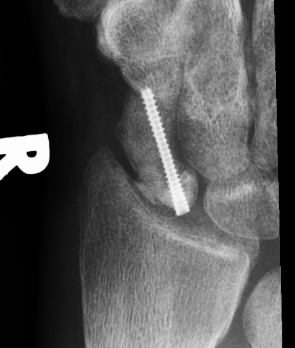

Post scaphoid ORIF

Proximal pole nonunion

Technique

Dorsal approach